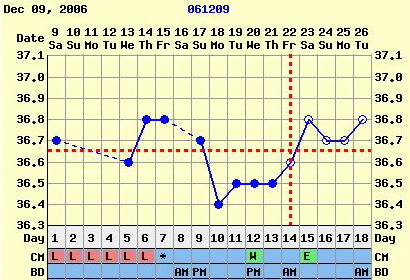

Nem tudom, hogy ez normális-e, miközben minden hormonom rendben, és a hőgörbe mutat pé-t. Meg van pozitív LH tesztem is...

Gaby: a Te görbéd elég cikkcakkos, szerintem később pé-zel...Végülis hathatott a párodnál már a gyógyszer, ha nem is drasztikusan, de már jobbak lehetnek az eredményei...